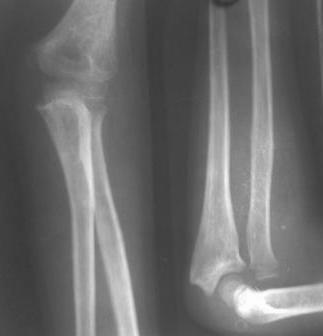

[Ortho] Застарелый вывых головки луча

Мальчик 10 лет, из отдаленного района, 3 года назад получил травму,

лечился уместного табиба. Об-но: движение в локтевом суставе в полном

обьёме, пронация и супинация предплечья не ограничены, ось предплечья

правильная, больного беспокоит только деформация- где

вывихнутая головка выступает под кожей . Планируются открытое

вправление, пластика кольцевидной связки местными тканями, фиксация

спицами.

1. На Р-грамме в профиль как будто лучевая кость смещена проксимально,

это не затрудняет вправление? Если да, то какие будут рекомендации?

2. После нашей операции может наступить контрактура, что можно сделать

для профилактики?